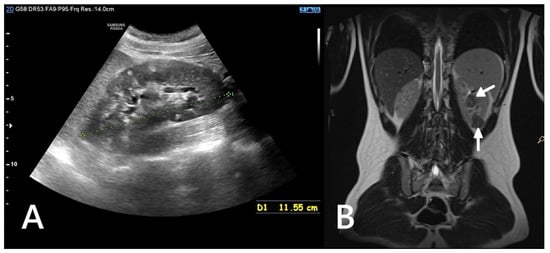

Potential complications of AML include haemorrhage (Wunderlich syndrome), the risk of which increases with the size and vascularisation of the lesion (Figure 2), and mass effect, which can cause discomfort or pain and may impair renal function by compressing urinary outflow or distorting normal renal parenchyma [19].

Figure 2. An ultrasound of a 10-year-old girl. A well-defined heterogeneous lesion, likely an AML, extending beyond the outline of the kidney. Within the lesion a fluid-filled area, likely a site of hemorrhage (*).